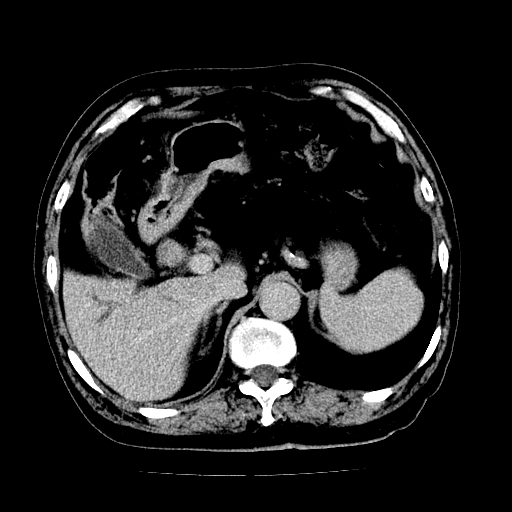

男,71岁,皮肤黄染四天。

肝内外胆管及胆总管上段扩张,考虑为梗阻所致,建议mrcp检查。

考虑胆总管癌并肝内外胆管扩张。

胰腺上端胆总管内见软组织影,强化不明显,结合临床,还是考虑低位梗阻性黄疸,胆总管癌可能性大